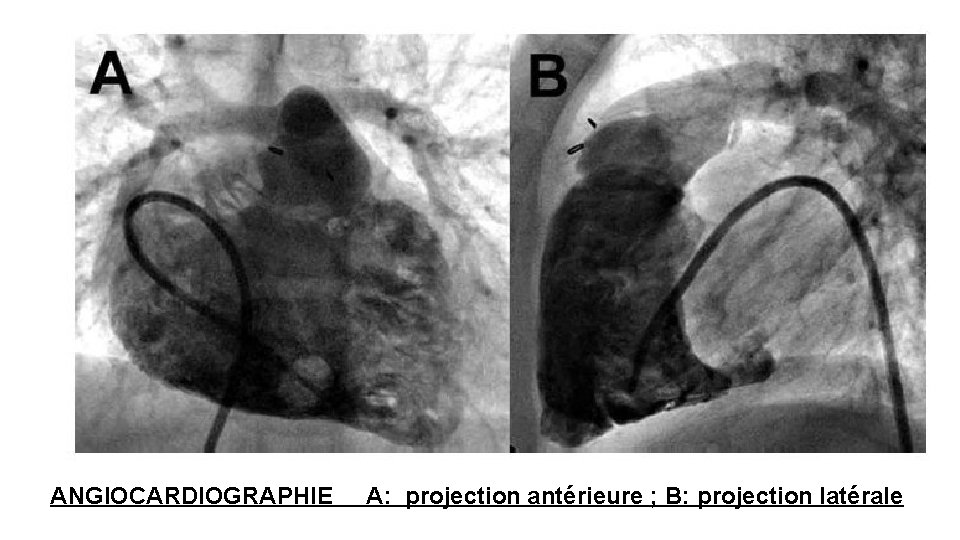

3 -ANGIOCARDIOGRAPHIE ET CORONAROGRAPHIE A - Technique • Consiste à filmer les cavités cardiaques et les artères coronaires rendues opaques aux rayons X par l'injection d'un produit de contraste riche en iode. • C'est un examen « sanglant » ou invasif Les incidents et accidents sont de trois types : • locaux, liés à la voie d’abord : hématome, thrombose veineuse, ou artérielle avec ischémie aiguë d'un membre. • cardiaques : perforation du myocarde, injection intramyocardique ou intrapéricardique • liés au produit de contraste : choc à l'iode, insuffisance rénale aiguë (diabétique surtout).

1 - Angiocardiographie sélective L'injection est faite sélectivement • soit dans une cavité droite à l'aide d'un cathéter monté par voie veineuse • soit dans une cavité gauche, le plus souvent par cathétérisme rétrograde transcutané de l'artère fémorale ou radiale. 2 - Coronarographie C'est l'opacification sélective des 2 troncs coronaires à l'aide de cathéters spéciaux introduits dans l'ostium coronarien gauche et droit. • soit par voie fémorale • soit par voie radiale Dans le même temps d'exploration, on opacifie la cavité VG (ventriculographie), ce qui permet de visualiser le comportement mécanique de sa paroi et de le corréler à l’état des artères coronaires.

ANGIOCARDIOGRAPHIE A: projection antérieure ; B: projection latérale